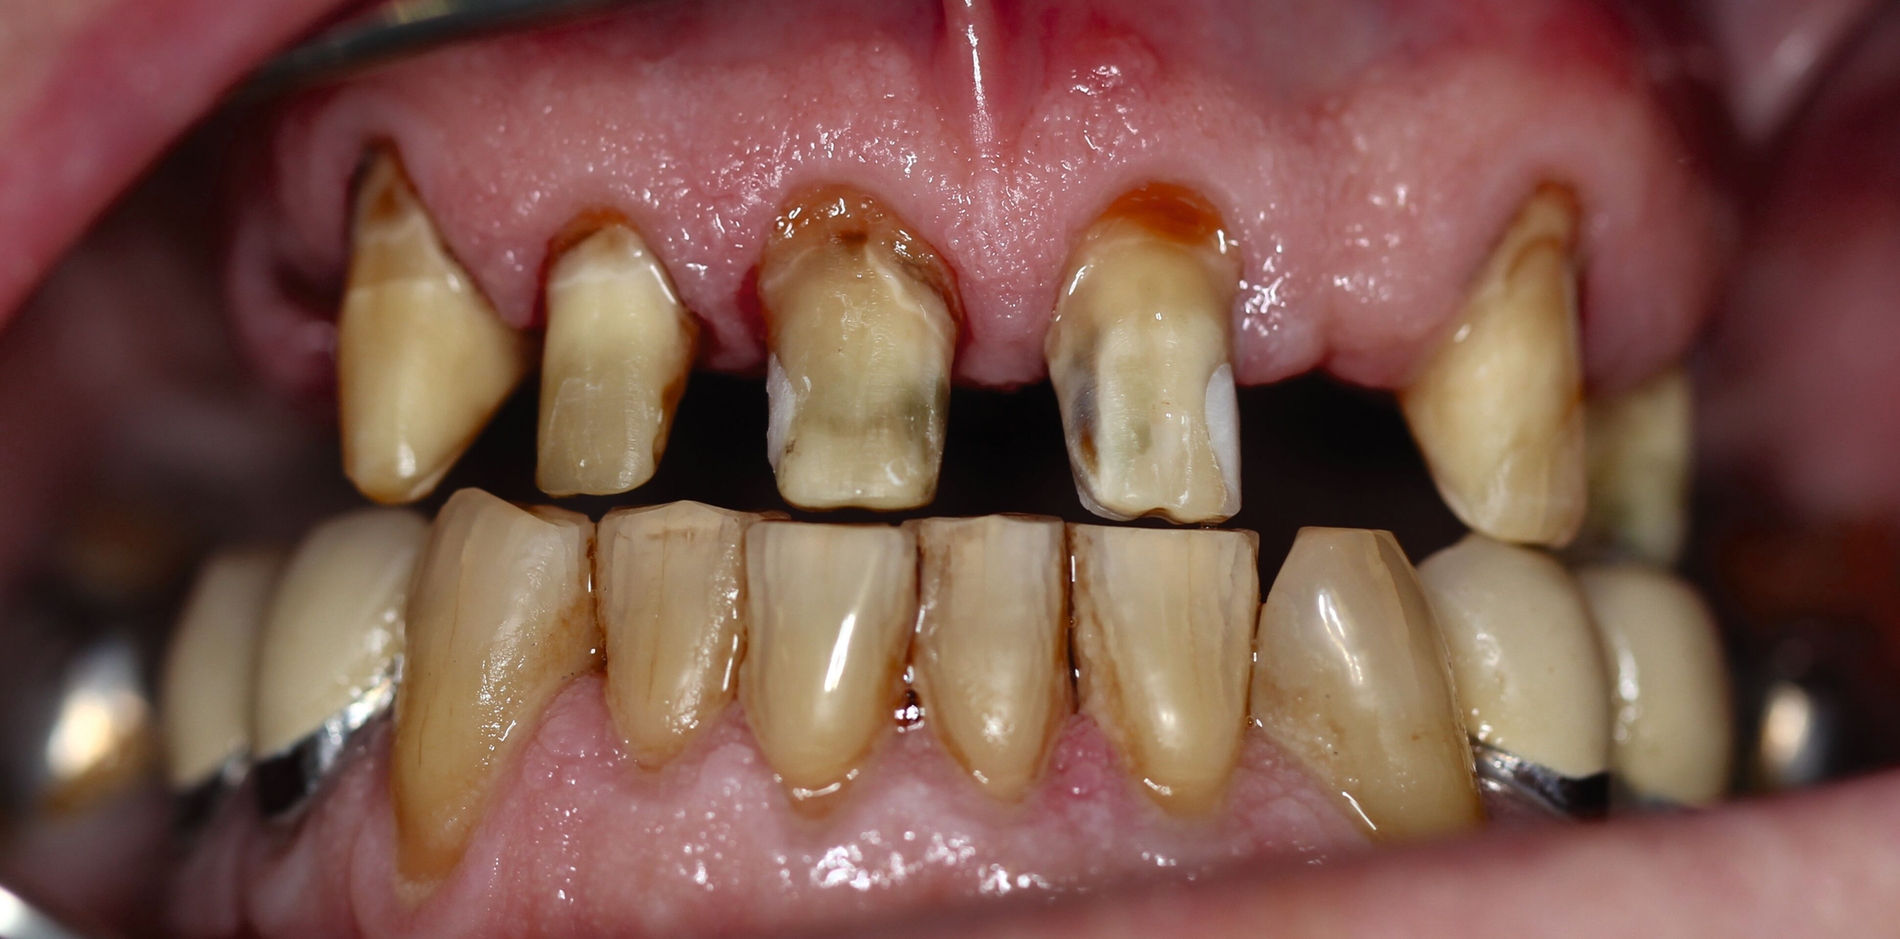

Der Patient stand unter der Dauermedikation von Metformin 500 mg, Ramipril 5 mg, Torasemid 10 mg, Metohexal 47,5 mg, Simvastatin 20 mg, Tamsulosin 0,4 mg und 3 mg Marcumar (INR 2,5–2,8) bei Zustand nach einer Bypass-Operation im Jahr 2019. Klinisch zeigten sich im Oberkiefer insuffiziente, verblockte und verblendete NEM-Kronen mit beidseitigen Gold-Extensionen distal, die über Geschiebe mit dem anterioren Anteil verschraubt waren (Abbildungen 1 und 2). Der Patient berichtete, dass die vorhandenen Kronen und Brücken 1984 eingesetzt worden seien.

Besonders auffällig war eine Dezementierung, die klinisch durch rechtsseitigen Druck und Zug mit einer Pinzette und daraufhin austretende Sulkusflüssigkeit in Regio 14 detektiert wurde. Da entsprechend des synoptischen Behandlungskonzepts [Naumann et al., 2010] bei prothetischer Neuversorgung eine gesamte Evaluation der Restpfeiler erfolgen muss, wurden zunächst die Kronen im Oberkiefer durch Schlitzen und Aufbiegen entfernt. Erst danach ließ sich deren Erhaltungswürdigkeit abschließend beurteilen.

So war der Zahn 14 tief kariös zerstört und nicht-erhaltungswürdig, was mit dem Bild der wahrscheinlich seit Längerem bestehenden Dezementierung korrelierte (Abbildung 3). Die Brücken im Unterkiefer wurden als suffizient befundet. Die Ruheschwebelage wurde mithilfe des Zielinsky-Zirkels auf 2 mm bestimmt. Parodontologisch zeigten sich stabile Verhältnisse. Ein Parodontaler Screening-Index (PSI) wurde erhoben (3-1-1-1-2-2). Der hier auffällige Zahn 14 wurde bereits zuvor beim klinischen Befund als nicht-erhaltungswürdig eingestuft und im Verlauf extrahiert.